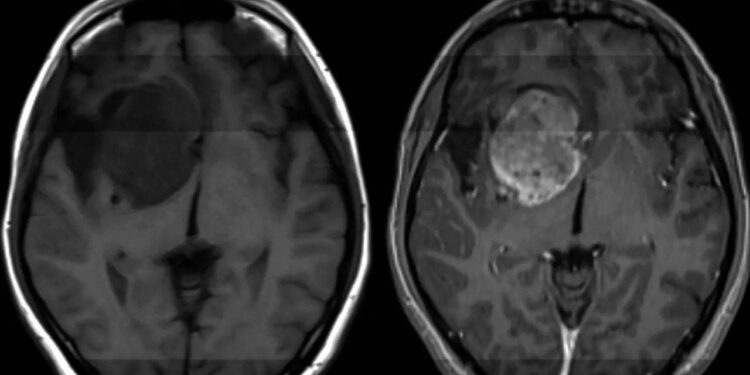

Glioblastom, tıbbın bugün hâlâ etkili bir çözüm üretemediği en yıkıcı kanser türlerinden biri olarak biliniyor. ABD’de her yıl on binlerce kişiye bu tanı konulurken, hastaların büyük bölümü tanıdan sonra yalnızca 12–18 ay yaşayabiliyor. Şimdi ise bilim insanları, bu tabloyu değiştirebilecek yeni bir biyolojik zayıf noktaya ulaştıklarını duyurdu.